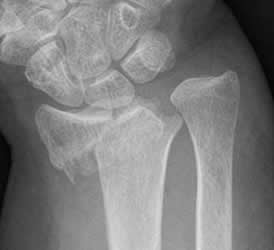

Fig 46. Fractura no desplazada.

Rx AP. Fracturas no desplazadas en las bases del 3º y 4º metacarpianos, cuyos fragmentos permanecen en contacto.